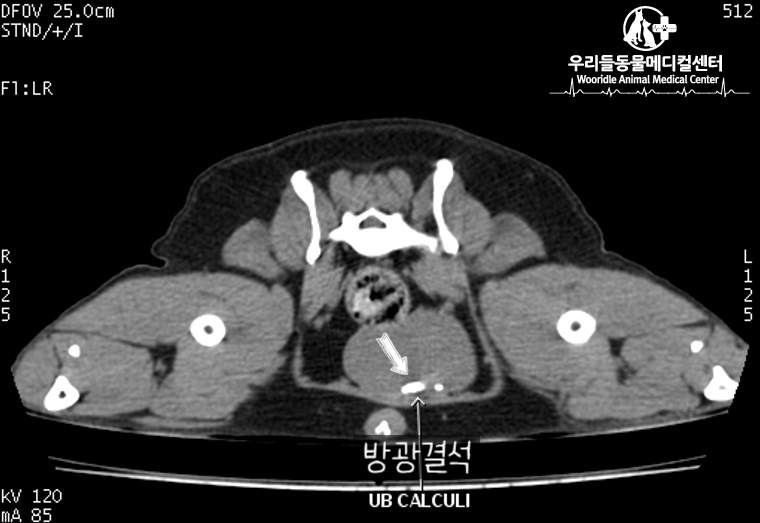

저희 강아지는 이제 막 2살이 된 작은 개로 이번에 방광결석이 생겨 방광내시경 시술을 받게 되었습니다.

먼저 개복수술이 아닌 방광내시경 시술을 받게 된 이유는 다음과 같습니다.당일 퇴원 : 어머니에게 애착이 심했기 때문에 개복 수술 시 5일간 입원하는 것이 다소 부담스러웠다.2. 빠른 회복: 개복하지 않고 카테터로 정교하게 시술 3. 향후 재발 시 개복수술 가능: 방광결석은 특성상 재발률이 높으나 매번 개복하면 방광에 손상이 있어 크기가 작아지고 향후 예후가 좋지 않을 수 있다는 이야기가 있다.